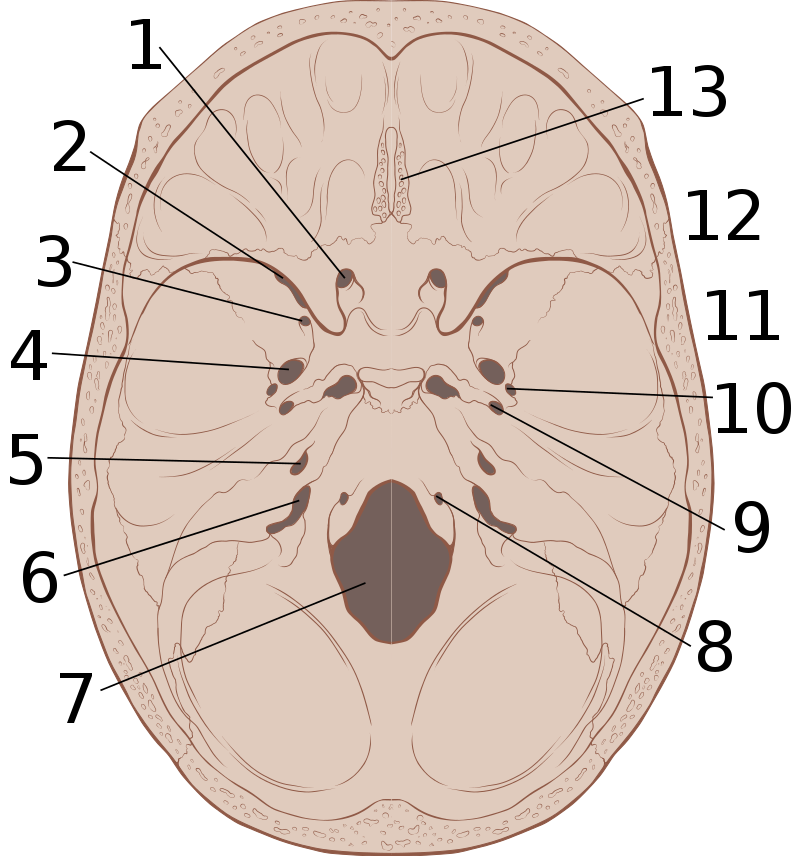

The most frequent type of intracranial herniation is a subfalcine herniation.

In subfalcine herniation the brain tissue protrudes through the falx cerebri.

Uncal herniation is another type of herniation, in which the temporal lobe uncus is displaced under the tentorium cerebelli.